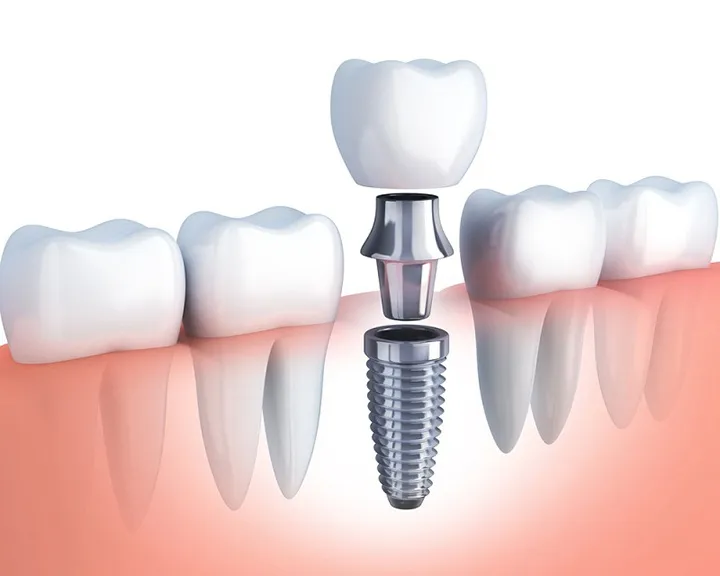

Điều trị tủy răng là biện pháp lấy đi phần tủy viêm hoặc đã bị phân hủy. Phần tủy chết này nằm ở phía sâu bên trong thân răng. Sau đó bác sĩ sẽ sạch khoảng trống bên trong răng cũng như tạo hình dạng cho ống tủy. Cuối cùng là trám lại phần ống tủy bị hở. Việc này sẽ cấu trúc răng được đảm bảo mà không cần phải nhổ bỏ đi

- Lấy tủy răng: Quy trình lấy tủy được thực hiện qua nhiều khâu. Đầu tiên, răng miệng được vệ sinh sạch sẽ và gây tê để giảm đau. Sau đó, bác sĩ đặt đế cao su để tách răng khỏi nướu. Điều này đảm bảo sự an toàn trong quá trình làm sạch tủy. Tiếp theo, ống tủy được làm sạch hoàn toàn thông qua quá trình bơm rửa.

- Trám bít ống tủy: Sau khi làm sạch, ống tủy sẽ được trám kín bằng vật liệu chuyên dụng. Từ đó đảm bảo không còn khoảng trống nào trong ống tủy. Đồng thời giúp bảo vệ răng khỏi nguy cơ nhiễm trùng sau này.